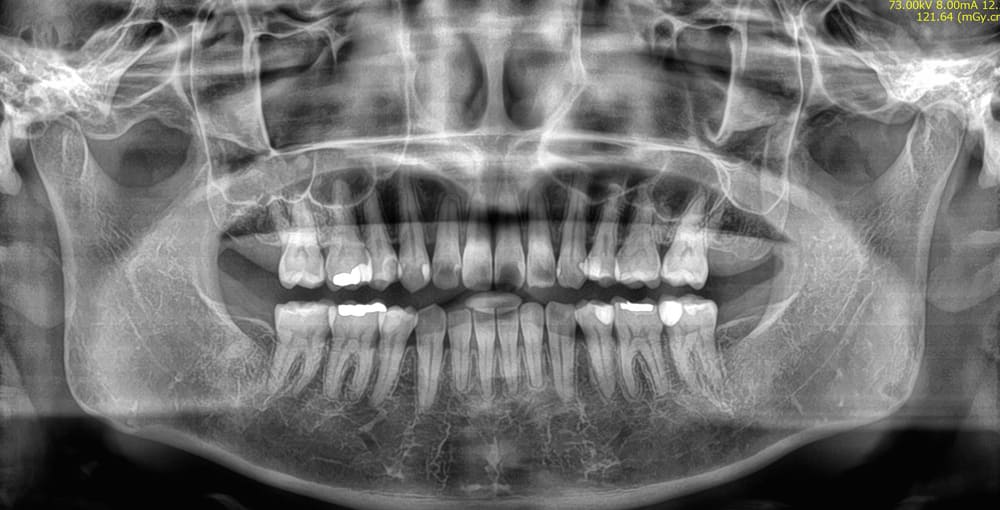

パノラマレントゲン写真です。

上下顎右側の親知らずは萌出しています。反対側はすでに抜歯されています。上顎右側第一小臼歯は根管治療が行われています。

こちらは治療後のパノラマレントゲン写真です。

親知らずは、4本とも抜歯されています。

今回親知らずを抜歯したのは、術後の咬合の安定のためです。

矯正治療後に親知らずが残っていると、親知らずが後ろからいわば盾のようになってせっかく後ろに下げた歯を前に押し戻そうとする力が働きます。

その親知らずを抜歯することによって、整った歯の後戻りを未然に防ぐことができます。

またこの症例では、根管治療(虫歯などで歯の根っこに薬剤による消毒等の処置をする治療)を行っていた歯を抜歯し、より健康な歯を残して治療を行えることができたことも、この症例の特出すべき点です。